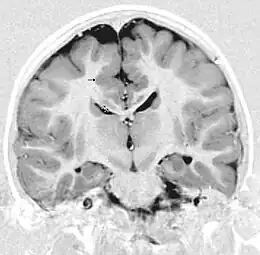

Description de cette image, également commentée ci-après

La polymicrogyrie est principalement une anomalie de l'organisation corticale des neurones probablement par un trouble de la migration des neurones à l'origine des dernières couches cellulaires du cortex cérébral : le cortex cérébral est plus épais avec de multiples circonvolutions.

Le diagnostic repose uniquement sur l'imagerie à résonance magnétique. La polymicrogyrie peut être isolée ou associée à d'autres anomalies : agénésie du corps calleux, schizencéphalie. Les diagnostics différentiels principaux sont la pachygyrie et la lissencéphalie.